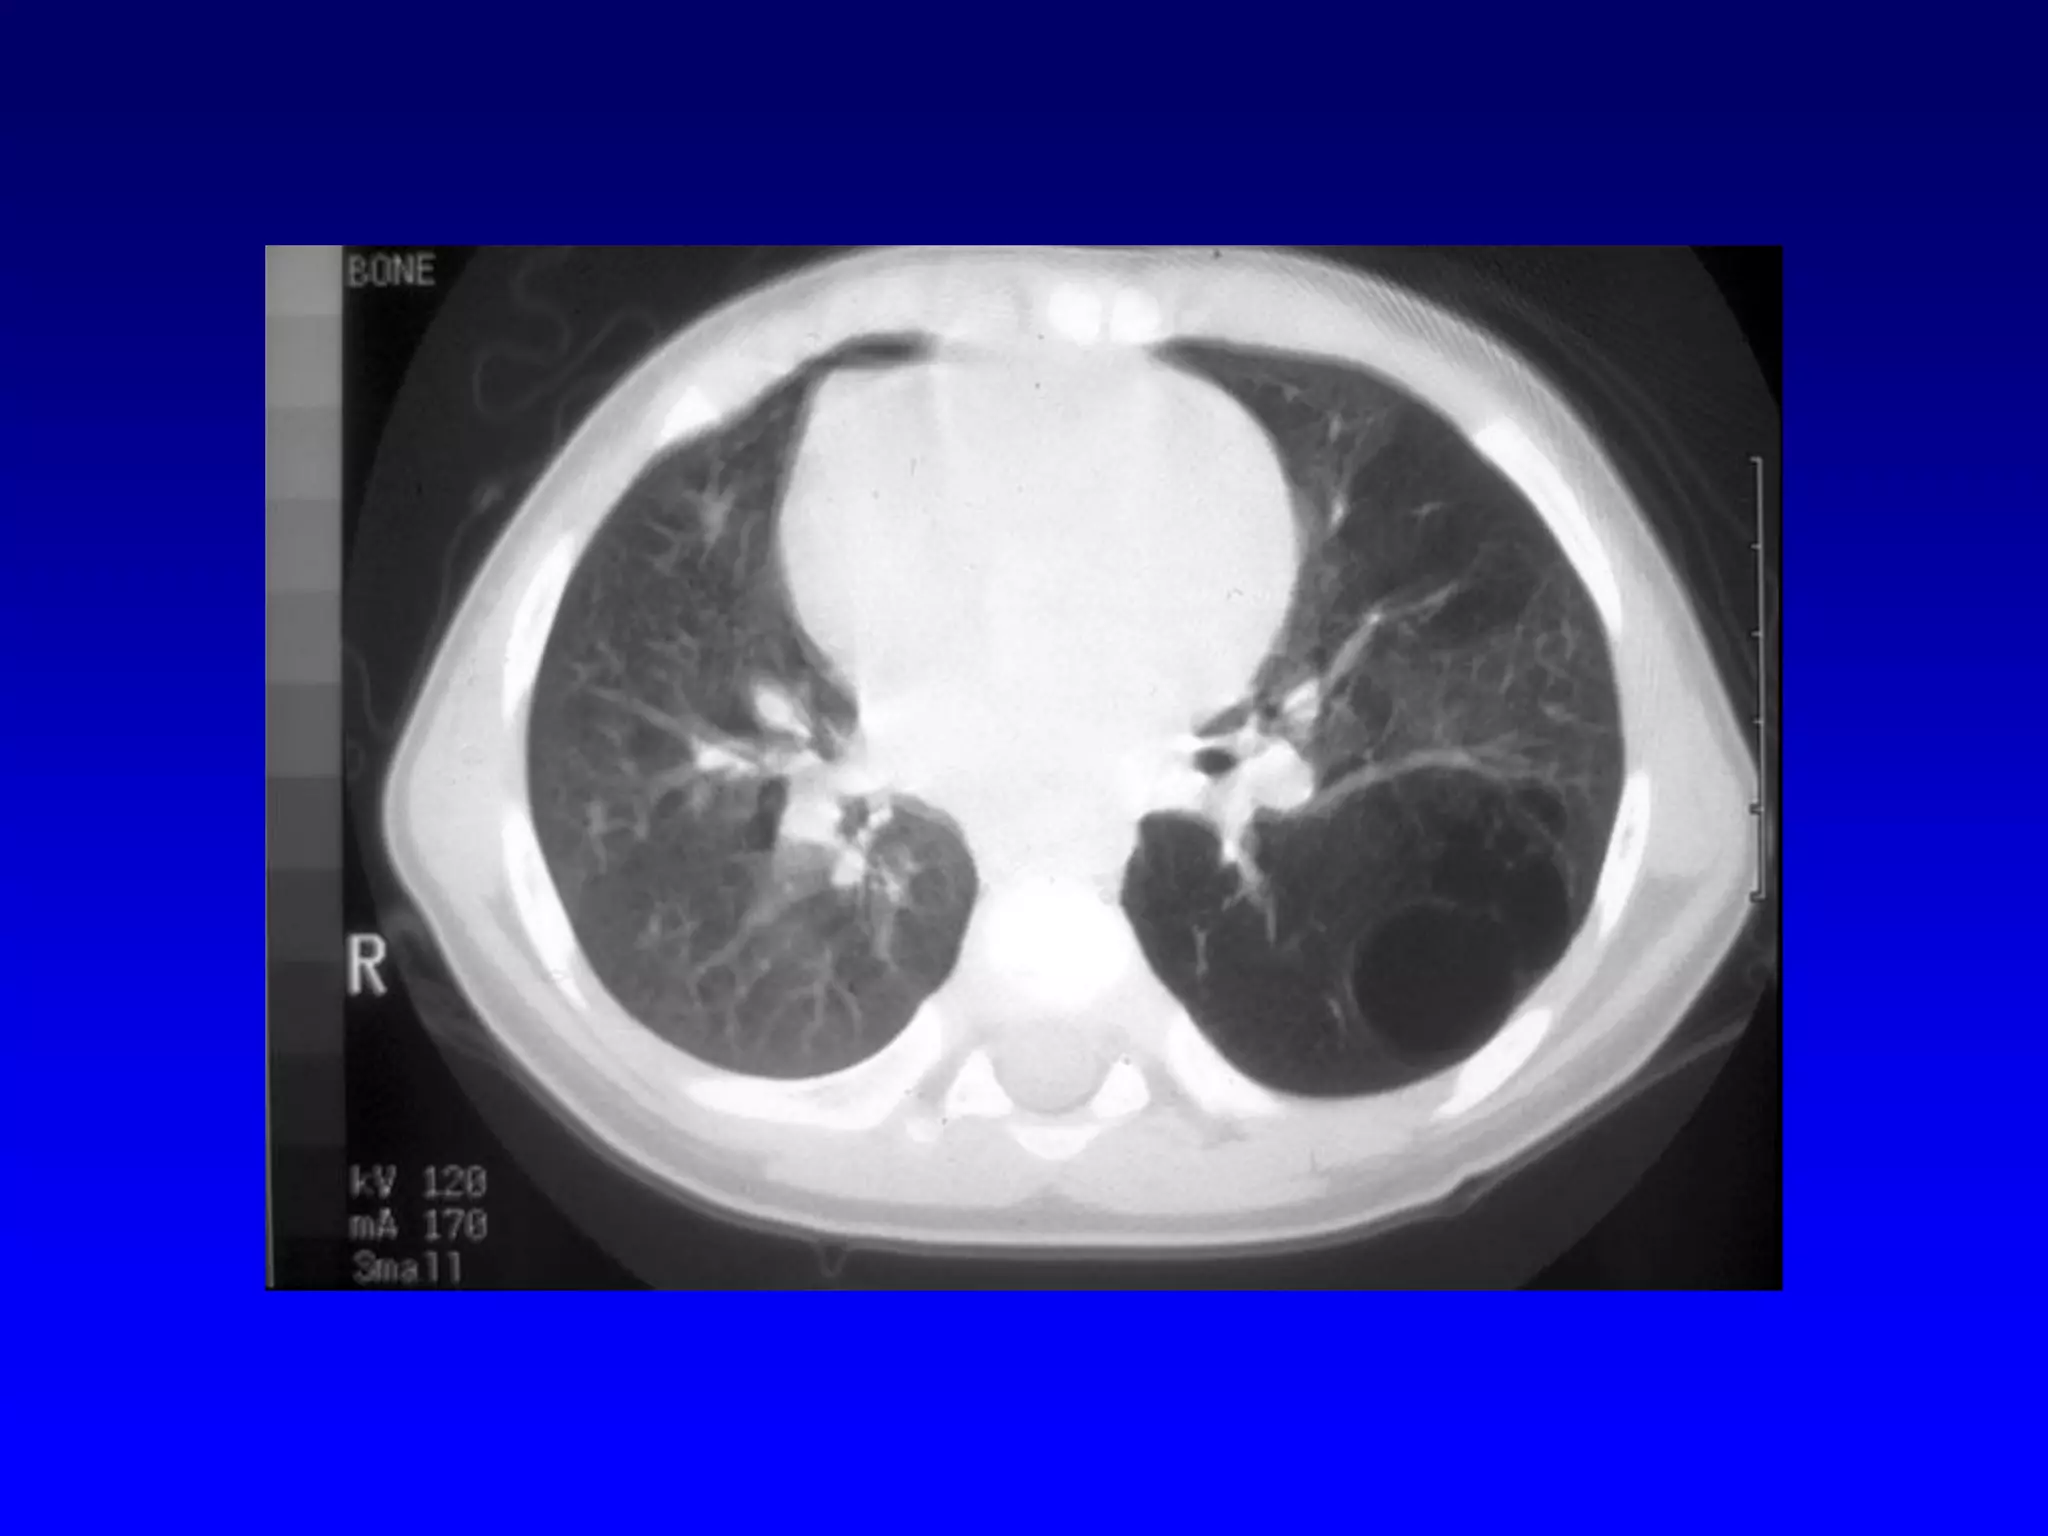

Atelectasis Left

Upper Lobe

Mediastinal shift to left

Density left upper lung field

Loss of aortic knob and left hilar

silhouettes

Herniation of right lung

Atelectatic left upper lobe

Forward movement of left

oblique fissure "Bowing sign"